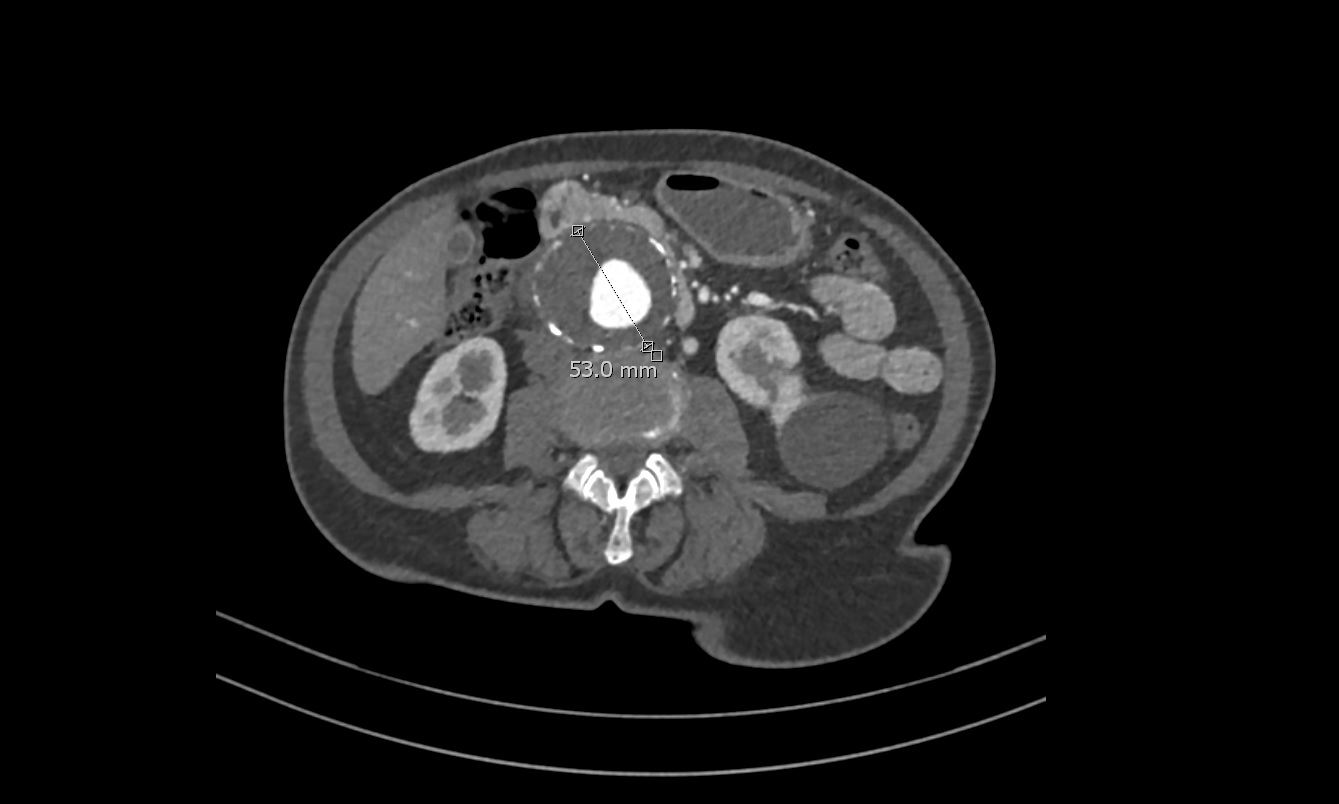

En Ecografía Clínica se aprecian, en la porción distal de la Aorta, imágenes sugestivas de aneurisma de Aorta abdominal con medidas aproximadas de 5.3 cm (anteroposterior) x 9 cm (longitudinal) con importante trombo intramural.

TC abdominal solicitado por Cirugía vascular confirma el diagnóstico de Aneurisma de Aorta Abdominal yuxtarenal de 9 cm de diámetro máximo, con trombo mural que se extiende distalmente hasta bifurcación de las arterias iliacas.